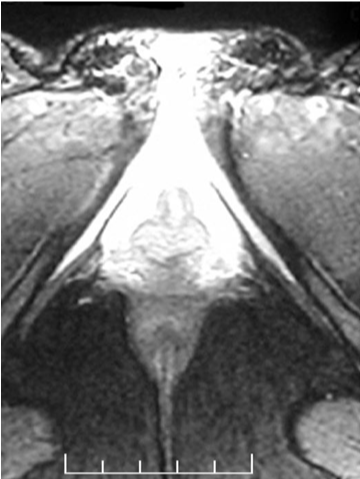

The first MRI of the clitoris

Odile Buisson

Helen O'Connel